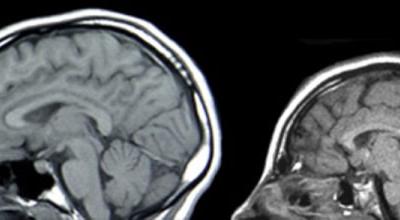

乳腺癌基因涉及大脑尺寸控制

乳腺癌基因涉及大脑尺寸控制(神秘的地球配图) (神秘的地球)据EurekAlert!:...